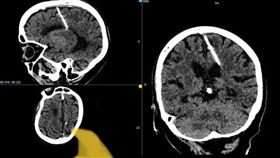

老婦腦部藏針80年!X光一照驚揭恐怖秘密

俄羅斯庫頁島(Sakhalin)一名80歲婦人到醫院...

2023/10/05 20:18